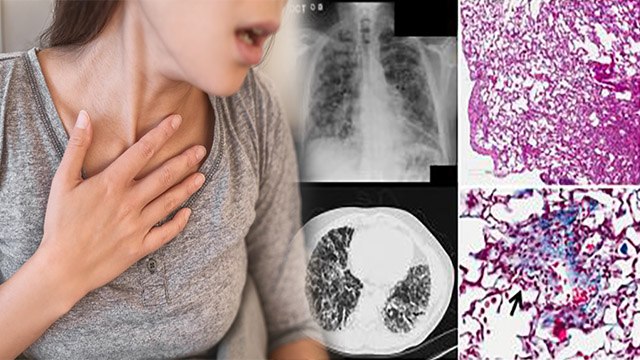

The second wave of corona in the country may have almost ended now but post covid problems still remain a matter of concern for many people. Even after recovering from corona, health problems are bothering many people. Doctors say that these problems of post covid can last from a few weeks to even months. कोरोना की दूसरी लहर देश में भले ही अब लगभग खत्म हो गई हो लेकिन पोस्ट कोविड समस्याएं अब भी कई लोगों के लिए चिंता का विषय बनी हुई हैं। कोरोना से ठीक होने के बाद भी कई लोगों में स्वास्थ्य संबंधी समस्याएं परेशान कर रही हैं। डॉक्टरों का कहना है कि पोस्ट कोविड की यह दिक्कतें कुछ हफ्तों से लेकर महीने तक भी रह सकती हैं। #Covid-19 #Coronavirus